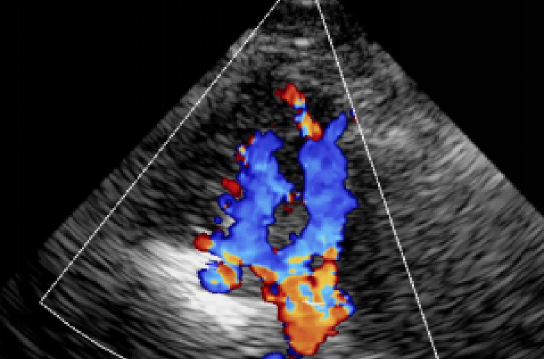

血管超声分析(VU)

- 斑块性质的判读

- 狭窄部位内中膜厚度测量

- 最狭窄管腔和参考血管的管腔直径测定

- 最狭窄管腔和参考血管的管腔面积测定

- 收缩期血流峰值流速测定,舒张期血流峰值流速的测定

- 阻力指数测定

- 频谱信号变化